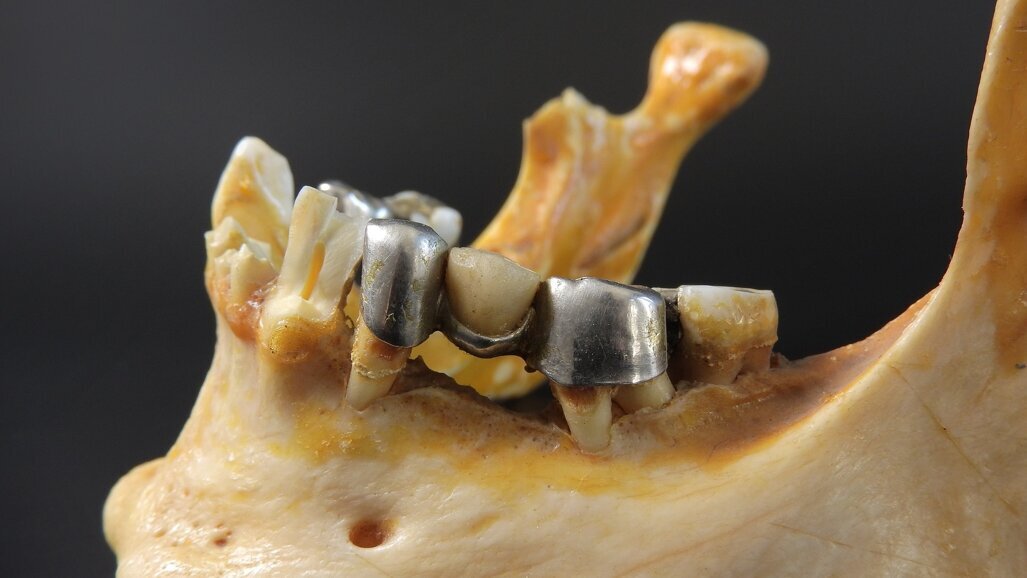

Autor prezentuje opis przypadku leczenia kompleksowego z planowaniem w centralnej relacji. Wykonano zabieg przeszczepienia pełnego bloku kostnego i ...